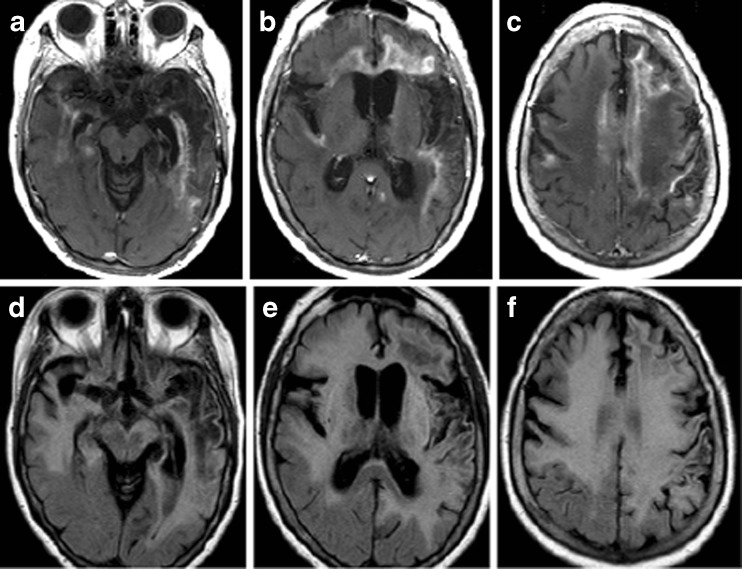

Case 2: A-79-Year-old Woman in SE

A 79-year-old woman presented in SE 3 months after being treated for HSVE. Brain MRI is shown in Fig. 3. HSV PCR and other infectious studies from the serum and CSF were negative. Anti-NMDAR IgG antibodies were detected in the CSF by immunofluorescence assay at 1:20 (normal: <1:1). With antiepileptic medications, steroids, plasma exchange, and intravenous immunoglobulin (IVIg), the patient improved and was discharged to skilled nursing care. Anti-NMDAR encephalitis and other immune-mediated encephalitides can be triggered by HSV [152]. In contradistinction to the initial HSVE, significant contrast enhancement on brain MRI has been observed [153], and may be a biomarker of autoimmune relapse, though future studies with greater patient numbers are needed. Importantly, these cases of clinical relapse after HSVE appear to respond favorably to immunotherapy [153].

Fig. 3.

Central nervous system autoimmunity following herpes simplex virus-1 encephalitis. (A–C) Extensive patchy postgadolinium enhancement involving the gray and white matter of the temporal and frontal lobes, and corpus callosum. (D–F) Corresponding fluid-attenuated inversion recovery (FLAIR) sequences demonstrate left > right temporal lobe cystic encephalomalacia and FLAIR hyperintense lesions